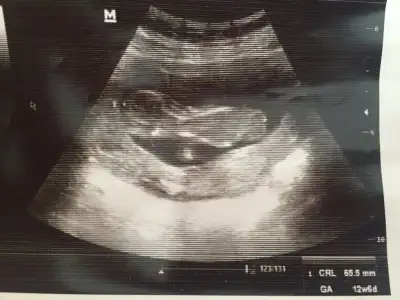

10 haftaya göre kız ama en iyi 11 12 13 haftalar olmalı tekrar USG paylasin6haftalik 10 ve 11haftalik görüntüsü

Teşekkürler canım 11 haftalık olanı hep erkek yorum yapıldı. Nasıl anlaşılıyor acaba ben hiç anlamıyorum10 haftaya göre kız ama en iyi 11 12 13 haftalar olmalı tekrar USG paylasin![]()

Bunun nubu görünmüyor o görünen kordonu11hafta

Teşekkürler yorumunuz içinBunun nubu görünmüyor o görünen kordonu